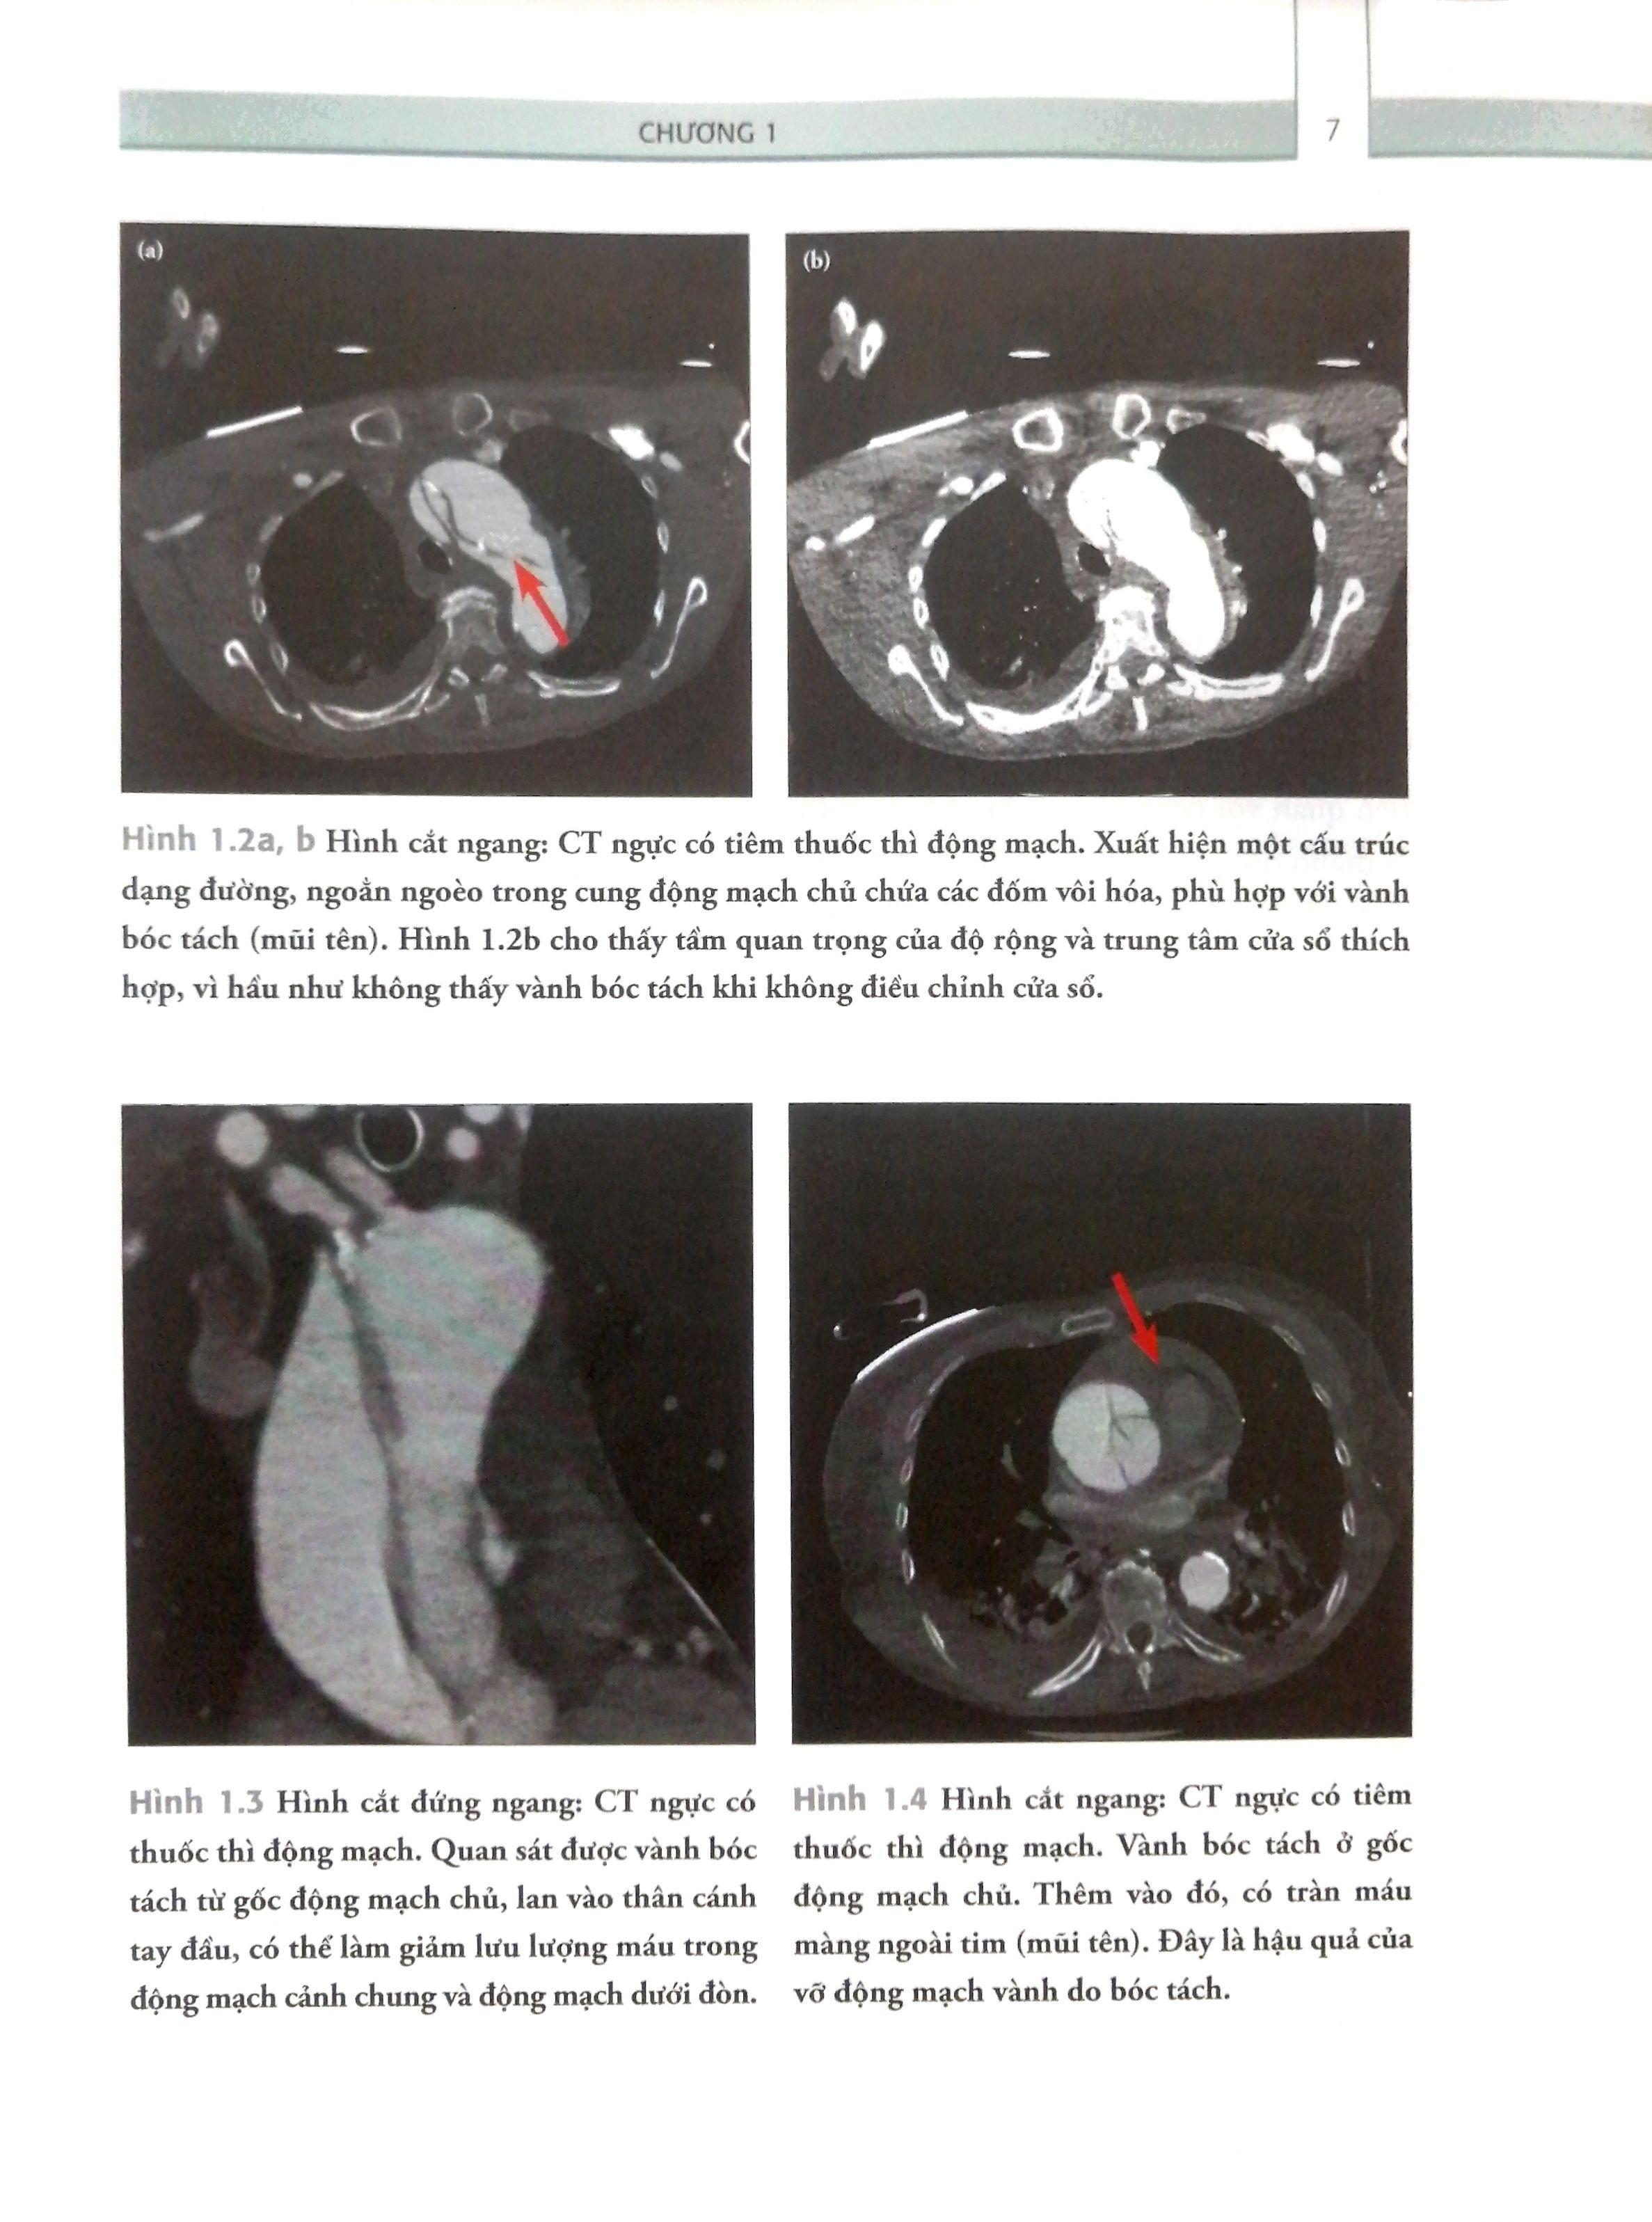

Mỗi trường hợp đều được trình bày dưới hình thức ca lâm sàng thực tế bao gồm cả bệnh sử và chỉ định chẩn đoán hình ảnh, các ví dụ hình ảnh học và bàn luận về chẩn đoán và xử lý cơ bản, nhấn mạnh vào các kết quả hình ảnh học quan trọng.

Cuốn sách này kết hợp giữa hình thức bàn luận về ca bệnh và các lời khuyên thực tế về lựa chọn loại hình ảnh cho trường hợp cấp tính. Ngoài ra, cuốn sách cũng đưa ra hướng dẫn viết báo cáo hình ảnh học và các kỹ năng cần thiết, tập trung vào các kết quả dương tính và âm tính để chuyển lại cho bác sĩ điều trị. Cẩm Nang Trực Chẩn Đoán Hình Ảnh sẽ là hành trang quan trọng mang đến những kiến thức và kỹ năng thực tế cho tất cả các bác sĩ.